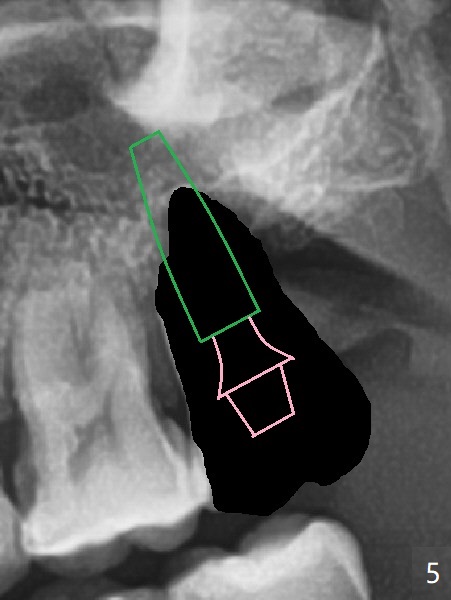

步骤二:选择大小长度合适基台(图五:粉红色)。